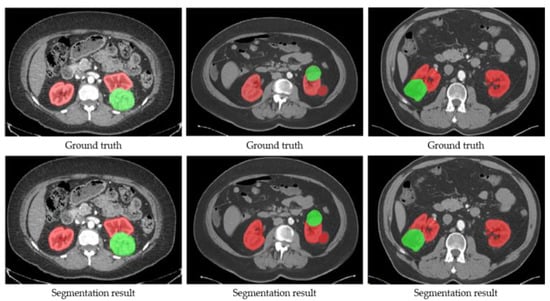

Firstly, the training and validation datasets are employed to update the weights and decide the optimal hyper-parameters of SegTGAN, respectively. Then, the performances of SegTGAN on the Kits19 and Kits21 testing datasets are measured. The ACC, DSC, and SEN of SegTGAN on the Kits19 and Kits21 datasets are 0.9728/0.9526/0.9539 and 0.9676/0.9507/0.9344, respectively. Some segmentation results of SegTGAN on Kits21 are shown in Figure 4.

Figure 4.

Examples of the segmentation results of SegTGAN on the Kits21 dataset. Red contour denotes the kidney and green contour denotes a tumor.